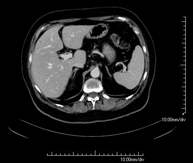

- Abdomen y pelvis- TC Abdomen Prueba diagnóstica que consiste en obtener imágenes del abdomen de alta definición anatómica (hígado, vesícula biliar, vía biliar, páncreas, bazo, estómago, intestinos, riñones, estructuras vasculares, vejiga, útero y ovarios, etc.) mediante el empleo de un equipo de TC (Tomografía Computarizada). Dichas imágenes se estudian posteriormente en una estación de trabajo que permite reconstrucciones bidimensionales en diferentes planos del espacio, y también reconstrucciones 3D (volumétricas). La mayoría de estudios requieren el empleo de contraste yodado para mejorar la definición de las imágenes. Prueba diagnóstica que consiste en obtener imágenes del abdomen de alta definición anatómica (hígado, vesícula biliar, vía biliar, páncreas, bazo, estómago, intestinos, riñones, estructuras vasculares, vejiga, útero y ovarios, etc.) mediante el empleo de un equipo de TC (Tomografía Computarizada). Dichas imágenes se estudian posteriormente en una estación de trabajo que permite reconstrucciones bidimensionales en diferentes planos del espacio, y también reconstrucciones 3D (volumétricas). La mayoría de estudios requieren el empleo de contraste yodado para mejorar la definición de las imágenes.